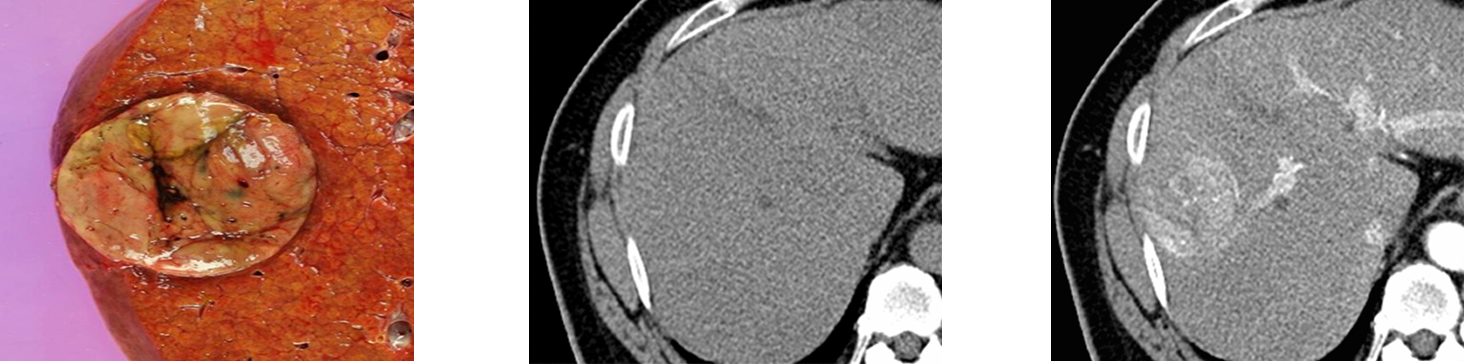

Hepatocellular Carcinoma (HCC)

______ is primary liver cell cancer.

It is most common in those with cirrhosis.

CT is modality of choice for diagnosis.

Hemangioma

An abnormal dense cluster of blood vessels.

Can be anywhere. Most common on the face, chest, back, and scalp.

Can be found in the liver.

Thought to be congenital.